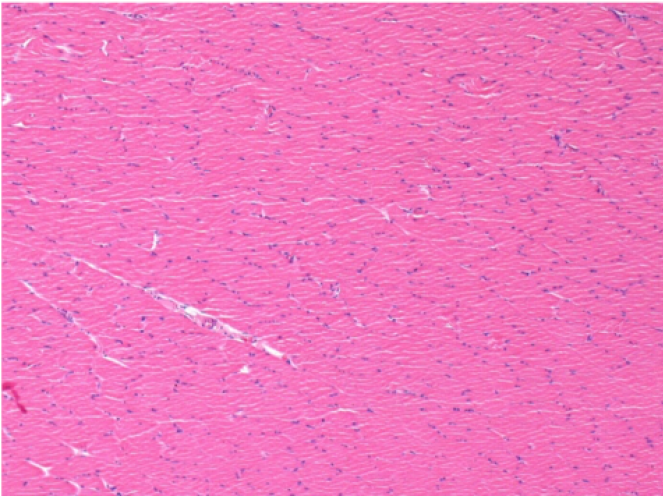

7 місяців (210 днів) після ін'єкції 0,1 мл Ендопіл в правий претибіальний м'яз.

Повна Restitutio ad integrum через 7 місяців